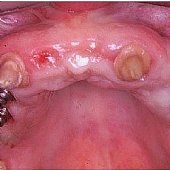

Bilder: Gesamtsanierung

• Geschliffene Zähne in Kombination mit Implantaten.

• Eingebrachte Implantate mit Durchtrittspfosten zur Aufnahme einer festsitzenden Keramikbrücke.